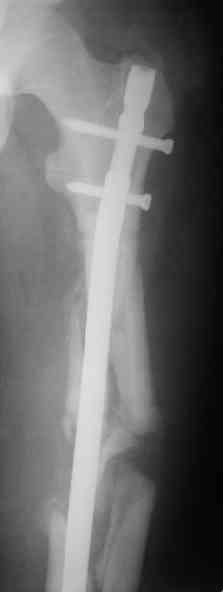

Вот несколько. С тисками и трубой на днях сделаем.

> Вот несколько. С тисками и трубой на днях сделаем.

Саша, последний штифт, пожалуй, перегнули?

> Саша, последний штифт, пожалуй перегнули?

Там заход сделан как для прямого штифта, не через вертел.

И правда, не через вертел. Тогда зачем гнули?